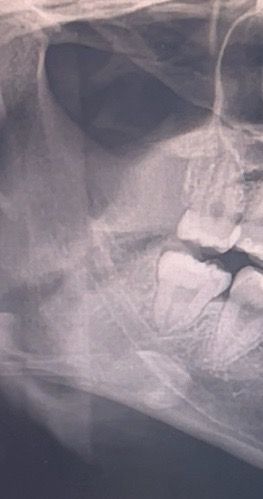

수직 매복 사랑니 발치 어려울까요??

머리는 조금 나와있고 잇몸이 머리 조금 덮고 있어요 잇몸 절개하고 뺄 것 같기는 한데 수평매복보다 훨씬 어려울까요...? 일주전에 수평매복 발치하긴 했습니다ㅠㅠ

• 1번 째 사진

뒤쪽으로 잇몸뼈 덮혀 있어 잇몸뼈 삭제해야 이가 빠질 가능성이 있습니다. 수직매복이 더 어려운 케이스도 있지만 지금 케이스는 그렇게 어려울 것 같지는 않습니다.

수평매복 사랑니보다 어렵지는 않습니다. 실제 잇몸을 열어봐야 확실하지만 아주 어렵진 않을겁니다.

저정도 사랑니는 난이도가 높은건 아닌거 같습니다. 치아 뿌리도 모아져 잇는 형태가 간단히 발치가 될것같습니다.

수직 매복치아의 발치는 난이도가 높은편에 속합니다.

하지만 불가능한것은 아니기 때문에 발치를 하고자 하는 병원에 문의를 하시고 발치를 하는것이 좋습니다.